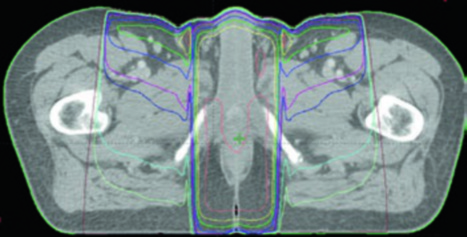

Terapia Ginecológica Pós-operatória

No cenário pós-operatório ginecológico, a introdução é objetiva: IMRT tornou-se a técnica de escolha para radioterapia adjuvante em neoplasias cervicais e endometriais. O capítulo ainda cita ensaio randomizado de fase III com redução significativa de toxicidade aguda gastrointestinal e geniturinária, melhora de qualidade de vida e menor irradiação de medula óssea em comparação com 3D conformacional. Para a versão completa, consulte o artigo dedicado à radioterapia ginecológica pós-operatória.

Terapia Ginecológica Definitiva

Na doença ginecológica definitiva, o livro mostra uma mudança de prática em andamento. A IMRT aparece como estratégia cada vez mais difundida, mesmo sem grandes estudos randomizados, apoiada por ensaios fase II e estudos controlados que sugerem efetividade e menor toxicidade. O capítulo percorre estadiamento, tomografia para planejamento, delineamento, órgãos de risco, avaliação do plano, guiagem por imagem e cenários de colo do útero, vagina e endométrio. Para aprofundar, leia o artigo de radioterapia ginecológica definitiva.

Tecnologias Avançadas em Ginecologia

No capítulo de tecnologias avançadas, os autores deixam claro o problema que estão tentando resolver: desfechos ainda subótimos em doença ginecológica locorregionalmente avançada e toxicidades que limitam a entrega do tratamento. Daí surgem os blocos do capítulo sobre guiagem por imagem, IMRT com preservação de medula óssea, replanejamento adaptativo, prótons e SBRT. Para acompanhar essa agenda tecnológica com mais detalhe, leia o artigo dedicado às tecnologias avançadas em ginecologia.